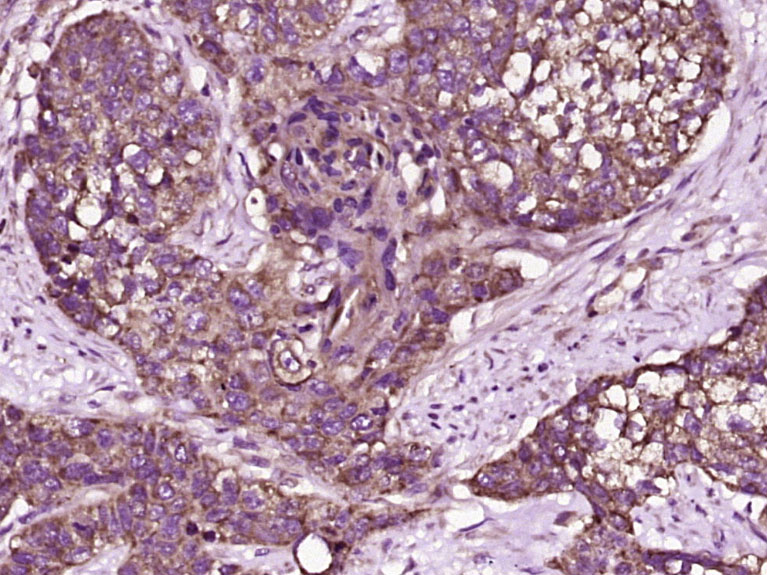

產(chǎn)品圖片

Paraformaldehyde-fixed, paraffin embedded (human gastric carcinoma); Antigen retrieval by boiling in sodium citrate buffer (pH6.0) for 15min; Block endogenous peroxidase by 3% hydrogen peroxide for 20 minutes; Blocking buffer (normal goat serum) at 37°C for 30min; Antibody incubation with (TFF2) Polyclonal Antibody, Unconjugated (bs-23857R) at 1:400 overnight at 4°C, followed by operating according to SP Kit(Rabbit) (sp-0023) instructionsand DAB staining.